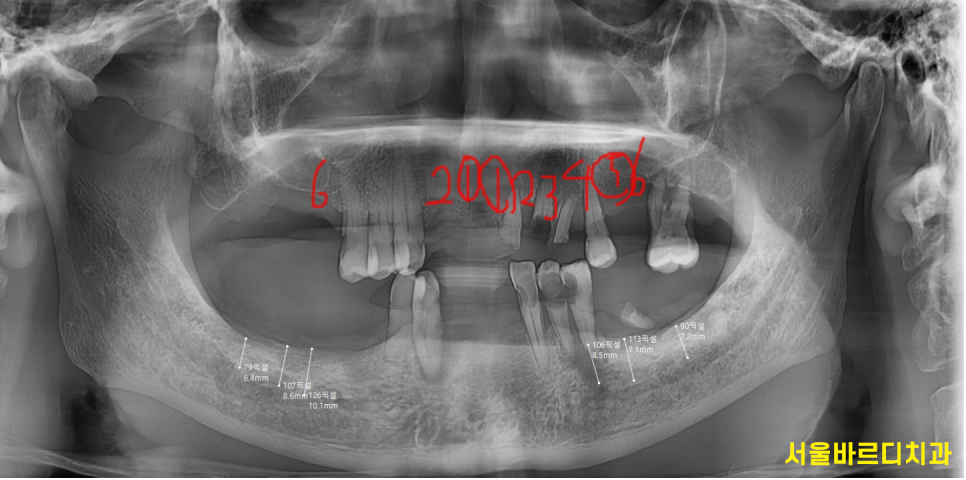

ct등을 통하여 임플란트 수술 계획이 결정되는데요.

임플란트는 뼈에 식립하기 때문에

골밀도와 잇몸 상태를 고려해 수술 방식을 결정해야합니다.

이에 따라 임플란트 재료도 달라질 수 있고

필요 시에 따라 잇몸치료나 뼈 이식이 진행될 수도 있습니다.

240423

사실상 진단만으로도 임플란트 식립 사이즈 , 개수 등이

결정된답니다.

오늘 환자분도 골밀도를 분석하여

남아있는 뼈의 양을 측정

임플란트 사이즈까지 적어 왜 뼈이식이 필요한지

설명드렸었거든요~~